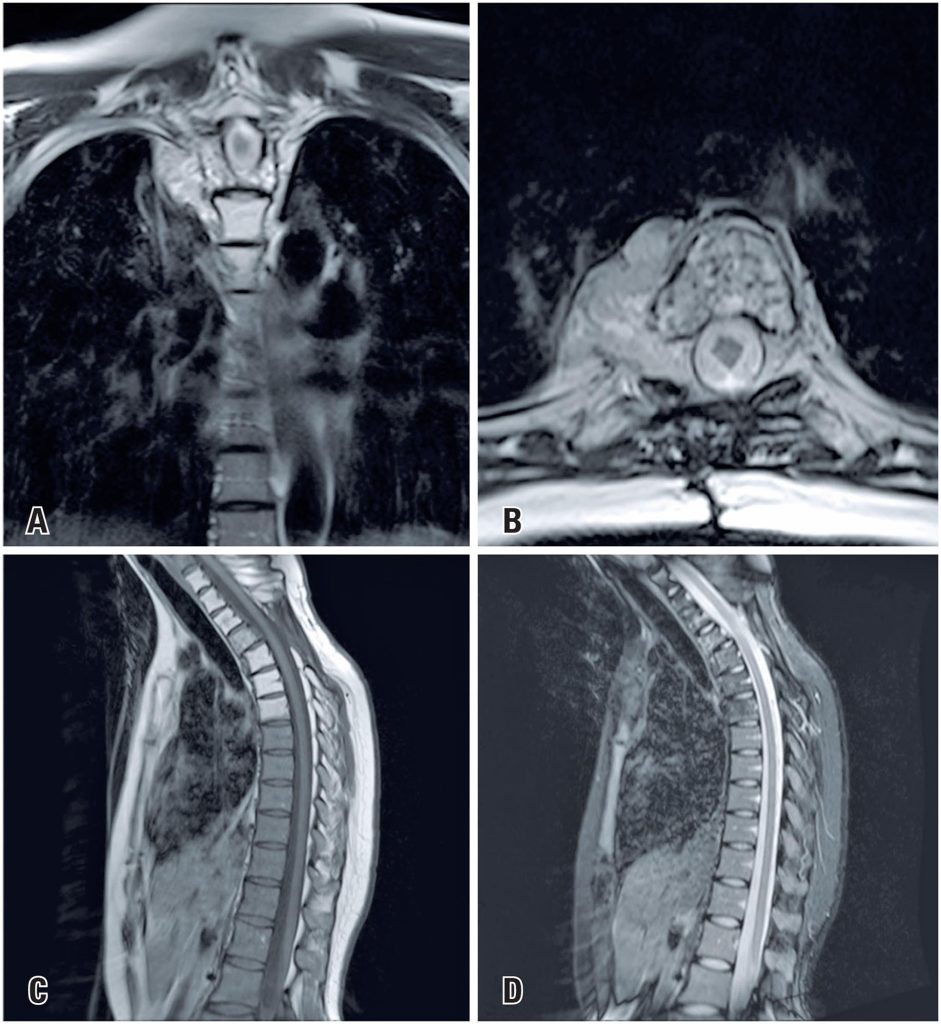

Myopericytomas are perivascular myoid neoplasms that rarely exhibit malignant characteristics. They usually arise in the dermis or subcutaneous tissue and exceptionally involve deep soft tissues, with spinal localization being rare. We report the case of a previously healthy 32-year-old pregnant woman who presented with pain in the interscapular region and progressive loss of lower limb strength. Magnetic resonance imaging revealed a solid neoplastic mass at the T3 level, with spinal canal invasion and spinal cord signal abnormalities. The pregnancy was terminated, followed by lesion embolization, decompressive laminectomy, and local radiotherapy. The patient completely recovered from her neurological symptoms. Thoracic spine myopericytomas are rare and have been poorly reported in the literature. No studies have described the aforementioned neoplasm in a pregnant patient. We report this case because of its peculiarity, evolution, and outcome.